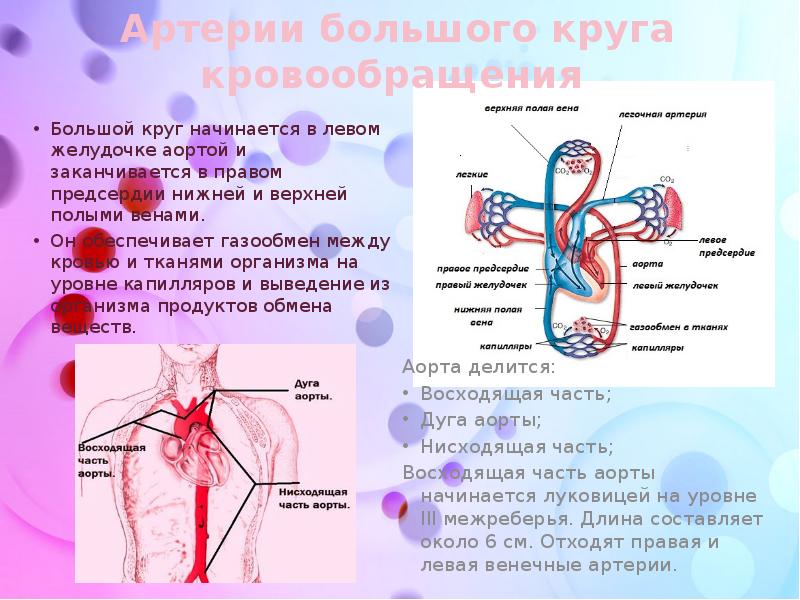

Особенности и диагностика левостороннего кровотока